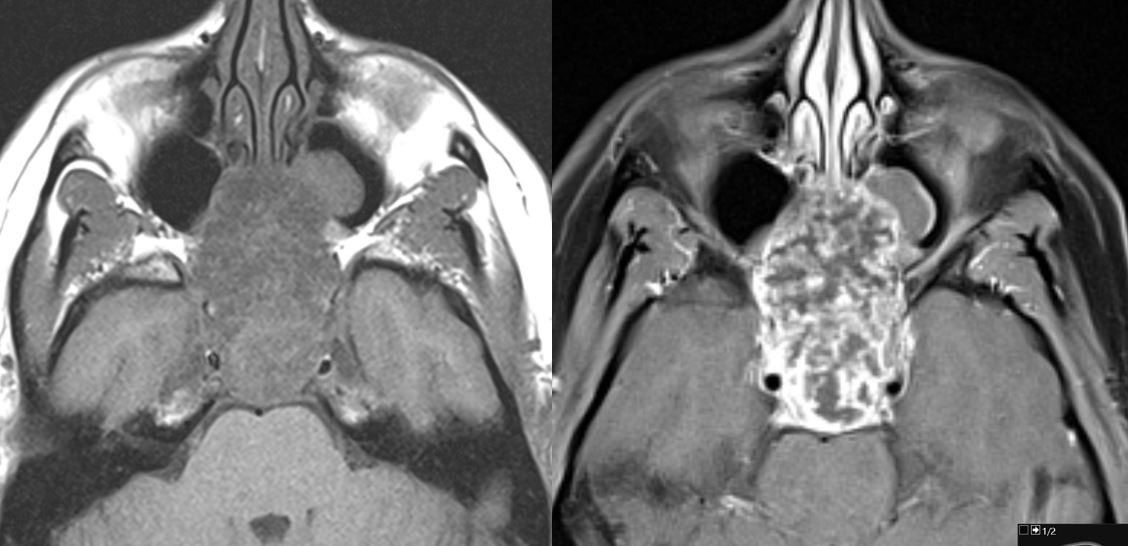

11 yo male with history of growth retardation and myopia presents with bradycardia and loss of consciousness.